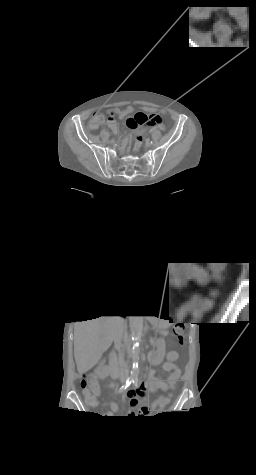

(a)

Refer to caption

(b)

(c)

(d)

Figure 3: (a) Axial (top) and coronal (bottom) slices of abdominal CT, HU range=(-400, 400) and (-150, 250) for ROI, (b) U-net (c) \partialU-net, (d) LIRE++

We perform extensive evaluation of LIRE++ and the baselines using image quality metrics such as PSNR and SSIM, which are computed for attenuation values, as well as MAE in Hounsfield Units due its importance for radiotherapy applications.

In Table 1 we report these metrics on the thorax & pelvic test set, and the corresponding box plots are provided in Figure 1. All metrics are computed for the full field of view region, i.e., the voxels which are present in at least half of the projections, which coincides with the field of view given by FDK and TV methods. Table 1 also contains mean total inference times per volume on NVIDIA A100 accelerator and the parameter counts, where in case of FDK and TV the parameter count of scatter pre-correction U-net is provided. In case of TV reconstruction, high inference time is partially due to multiple CPU-GPU memory transfers in ODL. Examples of thorax image slices of a ground truth image and the corresponding reconstructions from baselines and LIRE++ are presented in Fig. 2. Similarly, pelvic & abdominal image slices are presented in Fig. 3. The image samples demonstrate particularly well that LIRE++ is superior in reproduction of these soft tissue details which appear blurred in the baselines. Field-of-view in the reconstructions given by LIRE++ and \partialU-net is increased since the training loss is optimized over all voxels which are present in at least one projection. Extended FoV reconstruction quality for the voxels which are observed in at least one projection, but less than half of all projections, is slightly higher in LIRE++ reconstructions compared to \partialU-Net by appoximately 1 dB higher PSNR.